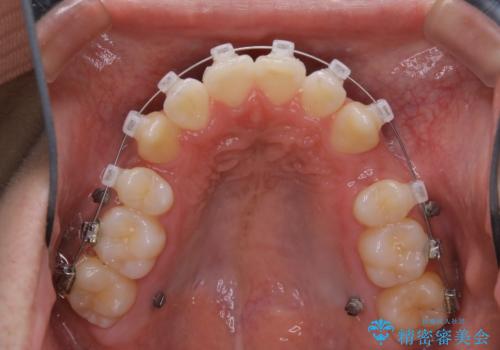

- 矯正装置

- クリア装置

親知らずと、前から4番目の歯を抜歯してワイヤー装置による矯正治療を行いました。

人前に出ることが多いため、当初は目立たない装置をご希望されていましたが、歯の移動距離が大きいため効率よく歯を動かせる表側の装置での治療をお勧めしました。すれ違ってしまっていた奥歯もしっかり治すことができました。